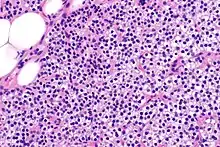

Las glándulas paratiroides están normalmente compuestas de células principales, adipocitos y células oxifílicas esparcidas.[27][14] Se piensa que las células principales son las responsables de la producción, almacenamiento y secreción de hormona paratiroides. Estas células aparecen claras y oscuras con un aparato de Golgi prominente y retículo endoplásmico. En micrografías con microscopio electrónico, las vesículas secretoras se pueden ver dentro y alrededor del aparato de Golgi y en la membrana celular. Estas células también contienen grasa citoplásmica prominente. Al inicio de la hiperplasia, estas células están descritas formando un patrón nodular con aumento de la maquinaria de síntesis de proteínas como el retículo endoplásmico y el aparato de Golgi. También se aumenta el número de vesículas secretoras que puede ser vistas y disminuye la grasa intercelular.[24] Las células oxifílicas también parecen hiperplásicas, sin embargo, estas células son mucho menos prominentes.

Bioquímicamente, hay cambios en la función entre las glándulas paratiroides hiperplásicas normales y nodulares. Estos cambios implican la expresión de protooncogenes y activación de rutas proliferativas, mientras que se inactivan las rutas apoptóticas.[28] En el tejido paratiroideo nodular, el aumento de la expresión de TGF-α, un factor de crecimiento, y EGFR, su receptor, da como resultado una proliferación agresiva y una mayor regulación a la baja de los receptores de vitamina de, que actúan para suprimir las secreciones hormonales.[25][8] Además, se aprecia que el marcador de proliferación Ki67 se expresa en gran medida en el estado hiperplásico nodular secundario. Se ha destacado que los genes supresores de tumores se encuentran silenciados o degradados en el tejido paratiroideo hiperplásico nodular. Uno de estos genes, p53, regula múltiples rutas de supresión de tumores y en la oncogénesis puede ser degradado por b-catenina. Esta ruta está en parte mediada por CACYBP, que se expresa en gran medida en la hiperplasia paratiroidea nodular.